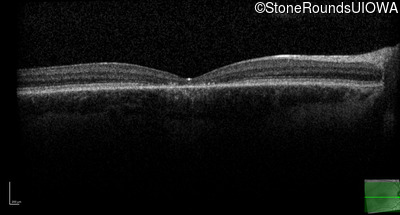

Age at visit: 17 years (Visit 2)

Age at visit: 21 years

Age at visit: 23 years

Age at visit: 25 years